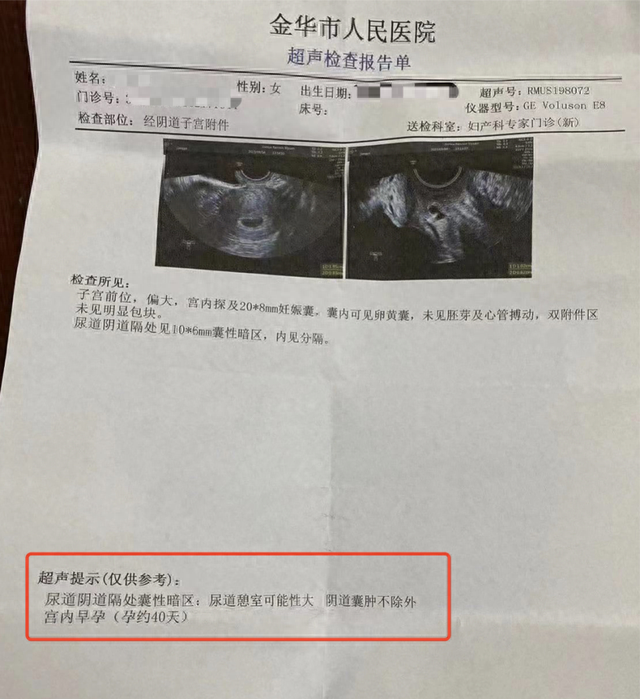

女子称b超未查出怀孕被开禁服药导致打胎,金华妇幼保健院:正协商|金华

图片尺寸640x699